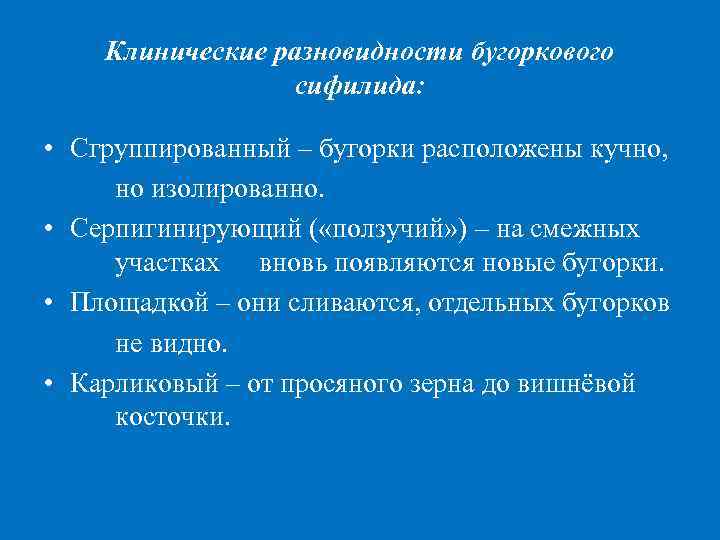

Поражения кожи представлены бугорковым и гуммозным сифилидами, и поздней третичной розеолой. БУГОРКОВЫЙ СИФИЛИД • залегает в сетчатом слое дермы, • полушаровидной формы, • размером с вишневую косточку, • тёмно‑ красного или синюшно-красного цвета, • поверхность гладкая, блестящая. q Спустя несколько нед - мес бугорок размягчается и изъязвляется с образованием округлой язвы с валикообразными краями. q Дно язвы очищается от распада, покрывается грануляциями и превращается в пигментированный по периферии атрофический рубец, на котором никогда не возникает новых высыпаний. q Группа рубцов имеет мозаичный вид.

Клинические разновидности бугоркового сифилида: • Сгруппированный – бугорки расположены кучно, но изолированно. • Серпигинирующий ( «ползучий» ) – на смежных участках вновь появляются новые бугорки. • Площадкой – они сливаются, отдельных бугорков не видно. • Карликовый – от просяного зерна до вишнёвой косточки.

БУГОРКОВЫЙ СИФИЛИД